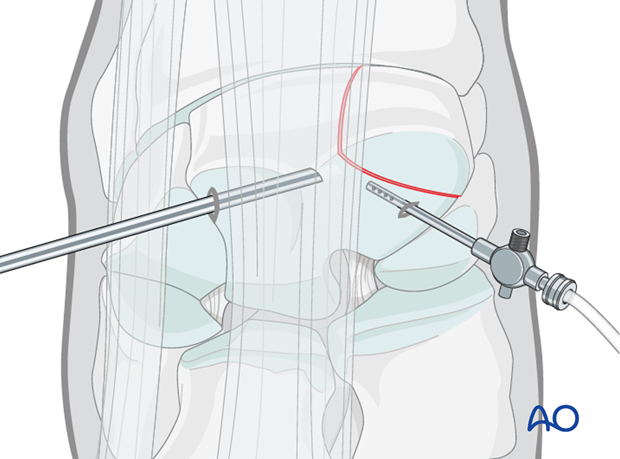

This procedure is performed with the patient placed in either lateral recumbency or dorsal recumbency, through the arthroscopic approach.

The proximal medial and lateral margins of the fracture are defined by arthroscopically guided percutaneous insertion of hypodermic needles.

It is important that these needles are placed perpendicular to the dorsal surface of the carpus to accurately delineate the fracture width.

An 18 gauge spinal needle is subsequently placed midway between these two needles close and parallel to the proximal articular surface and directed across the midpoint of the fracture as close to 90 degrees as possible. This needle is the most important directional guide for implant placement.

The configuration of most frontal plane slab fractures of the radial facet are such that the tip of the needle usually lodges in the palmar fossa of the bone and can be implanted in the non-articular surface to stabilize the spinal needle sufficiently.

Once the spinal needle has been placed, a further 18 gauge needle is inserted parallel to it into the carpometacarpal joint.